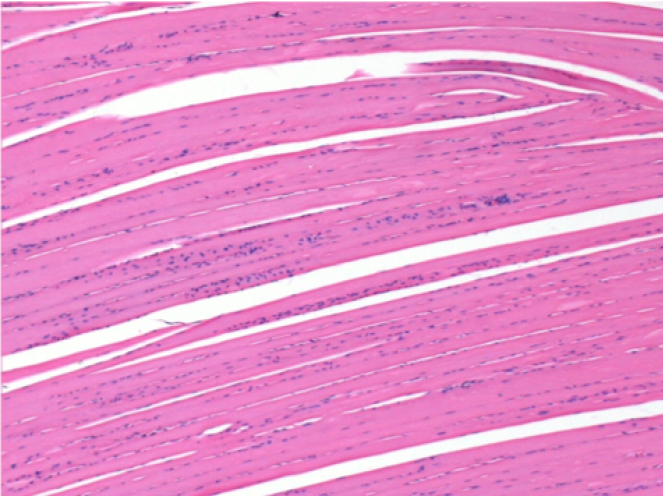

بعد 10 أيام من حقن إندوبيل

10 أيام بعد حقن إندوبيل 0.1 مل في العضلة أمام الظنبوب الأيمن.

هنا قد ترى تشكيل الفجوات التي تحيط بها الخلايا اللمفاوية. الفجوات تختلف عن نخر الأنسجة. يرتبط وجود الخلايا اللمفاوية بنفاذية أغشية الخلايا.

L : Control-100xD10

R:100xD10

R :200xD10

R :400xD10